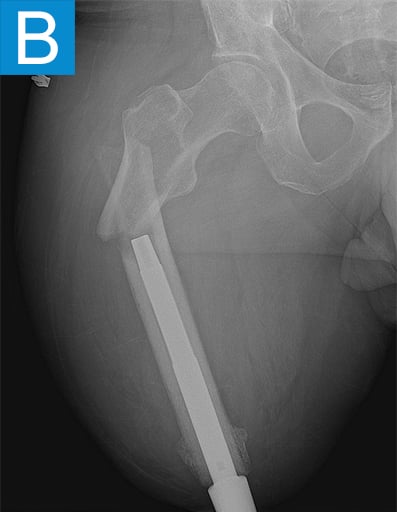

He started progressively loading the implant at 2 weeks and received his full prosthetic leg with simple hinged knee at 6 weeks. At 3 months he no longer used assist devices and at 3.5 months his prosthesis was changed to a microprocessor-controlled knee. Shortly after receiving the new knee, he stumbled stepping over a ledge and fell, sustaining a subtrochanteric proximal femur fracture (Figure 2b). The fracture extended to the tip of the implant, which remained stable in the bone. He underwent open reduction and internal fixation of the femur fracture with a proximal locking plate (Figure 2c). He did not wear the prosthetic leg for 10 weeks, when he began gradually loading the femur. He resumed full weightbearing without assistive devices about 6 weeks later.

Figure 2. Postoperative X-rays shows (A) a femoral osseointegration implant; (B) a subtrochanteric proximal fracture; (C) the femur fracture repaired by open reduction and internal fixation with a proximal locking plate.

Periprosthetic fracture around osseointegrated stems is not surprising, given the stress concentration that occurs proximally to the stem. The incidence is around 5% and mostly due to falls [2]. The stems themselves are nearly always stable in the bone because the osseointegration is robust. This was true in this patient despite less than 4 months of integration time. Thus, the stem can nearly always be maintained and the fracture fixation follows familiar principles. Many periarticular plating options now exist for the femur so that screws can be placed into the diaphysis around the stem to achieve proximal fixation. With stable fixation the healing is usually routine because the forces on the fracture are minimal without the prosthesis attached. Patients usually go back to their prior level of function once healed [2].